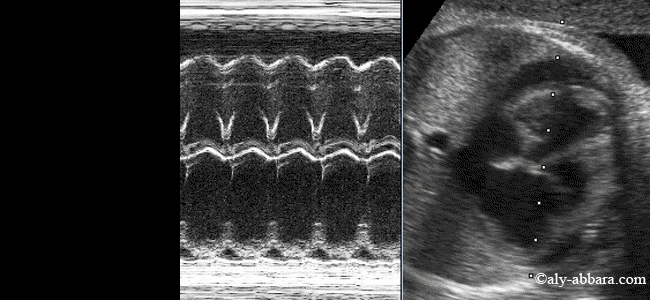

Image échographique en temps réel et en mode TM mettant en évidence

une tachycardie supraventriculaire avec épanchement péricardique chez

un fœtus âgé de 33 semaines d'aménorrhée.

La qualification de supraventriculaire a été donnée à cette tachycardie fœtale car le mode TM montre que les ventricules et les oreillettes battent à la même fréquence (237 battements par minute dans cet exemple).

L'épanchement péricardique fait partie des manifestations habituelles de l'insuffisance cardiaque. Dans le cas présent, l'insuffisance cardiaque est la conséquence de cette tachycardie fœtale supraventriculaire sévère : cœur fœtal battant en permanence à une fréquence de (220 à 240) battements par minute

La présence de la tachycardie fœtale est à l'origine de la diminution des variations des volumes systoliques et diastoliques des quatre cavités cardiaques,

d'où les signes de l'insuffisance cardiaque fœtale (épanchement péricardique, ascite, hépato-splénomégalie, œdème des téguments cutanés, polyhydramnios et épaississement œdémateux du placenta.